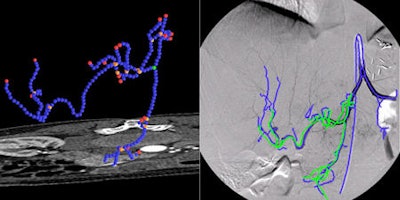

Also of note for interventional radiologists, is 2D/3D registration of angiographic images and catheter tracking for guidance of endovascular procedures. A series of studies using this technique will be presented by different groups who will describe their research in the navigation of catheters inside the vasculature for stent placement using a combination of preoperative CT angiography, intraoperative x-ray, and intravascular ultrasound.

"Such techniques allow doctors to make better decisions when faced with complications, through improving precision of stent placement, reducing the amount of x-ray radiation, and obviating the need for contrast injection," Navab said.